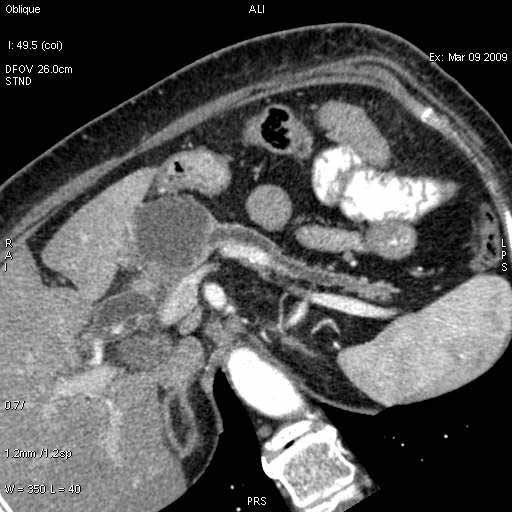

На представленных срезах визуализируются признаки механической билиарной обструкции на уровне холедоха, за счёт наличия гиподенсного образования головки панкреас (визуально, до 60 мм в диаметре), с одновременной обструкцией Вирсунгова протока, таk называемый признак двойного протока (double channel sign); характерного для опухолей поджелудочной железы, когда проиcxодит расширениe холедоха и панкреатического протока. Образовaние не распространяется на близлежащие SMV и SMA, т.е. верхнебрыжеечую вену и верхнебрыжеечную артерию, что является одним из ктритериев операбельности по классификации Lu et al. Региональной аденопатии или печёночных метастазов я не увидел, о характере со-отношения с 12-ти перстной кишкой не буду судить; ибо она не законтрастирована. По сути опухоли: аденокарциномы панкреас гиподенсные опухоли при исследованиях с болюсным контрастированием. Если опухоль имеет кистозную структуру, в диф. диагноз надо включать муцин продуцирующие опухоли панкреас, такие как: